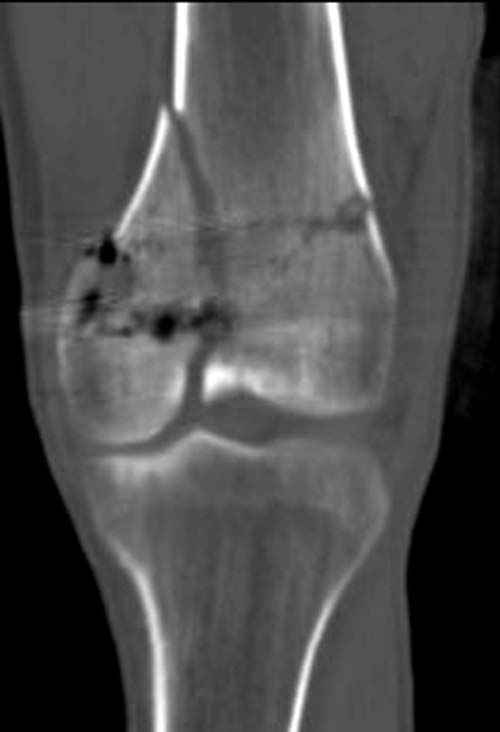

У молодого человека огнестрельное слепое ранение н/3 правого бедра. Поступил в клинику с внутрисуставным многооскольчатым Т-отразным переломом дистального отдела бедренной кости. Дополнительно на  СТ-исследовании обнаружен перелом внутреннего мыщелка Hoffa со смещением.<br><br>

Больной взят в операционную на второй день, где из небольшого медиального доступа выполнена артротомия коленного сустава. Произведена репозиция отломков, фиксация винтами. Попутно удалена пуля. Первым делом была достигнута репозиция медиального мыщелка (перелома Hoffa, где коронарная плоскость перелома трудно поддается закрытой репозиции и фиксации. ) Затем была достигнута идеальная репозиция суставной поверхности бедра и фиксация компрессирующими headless  screws.<br><br>

Дистальный отдел бедра был дополнительно фиксирован buttress пластиной с медиальной стороны из того же разреза. Для усиления фиксации латеральной колонны -  с латеральной стороны закрытым способом из минидоступа установлена еще buttress plate.  Пулевой канал дополнительно не подвергался хирургической обработке.<br><br>